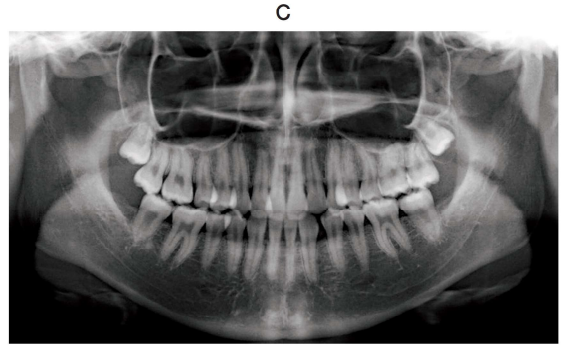

118回 A-22

21 歳の女性。前歯の咬み合わせが悪いことを主訴として来院した。診断の結果、上顎両側第二小臼歯を抜去後、マルチブラケット装置を用いた矯正歯科治療を行うこととした。初診時の顔面写真(別冊No. 4A)、口腔内写真(別冊No. 4B)及びエックス線画像(別冊No. 4C)を別に示す。セファロ分析の結果を図に示す。

上顎のマルチブラケット装置と併用する適切な矯正装置はどれか。 1 つ選べ。

解答:c

解説:

セファロ:上顎骨が小さい、下顎前突

叢生:上顎が叢生、2番が交叉咬合

臼歯関係:Ⅲ級

交叉咬合を改善したいので、上顎を広げることができるcのクワドヘリックス装置が正解。

急速拡大装置、上顎前方牽引装置は小児。ヘッドギアは上顎前突に適用。